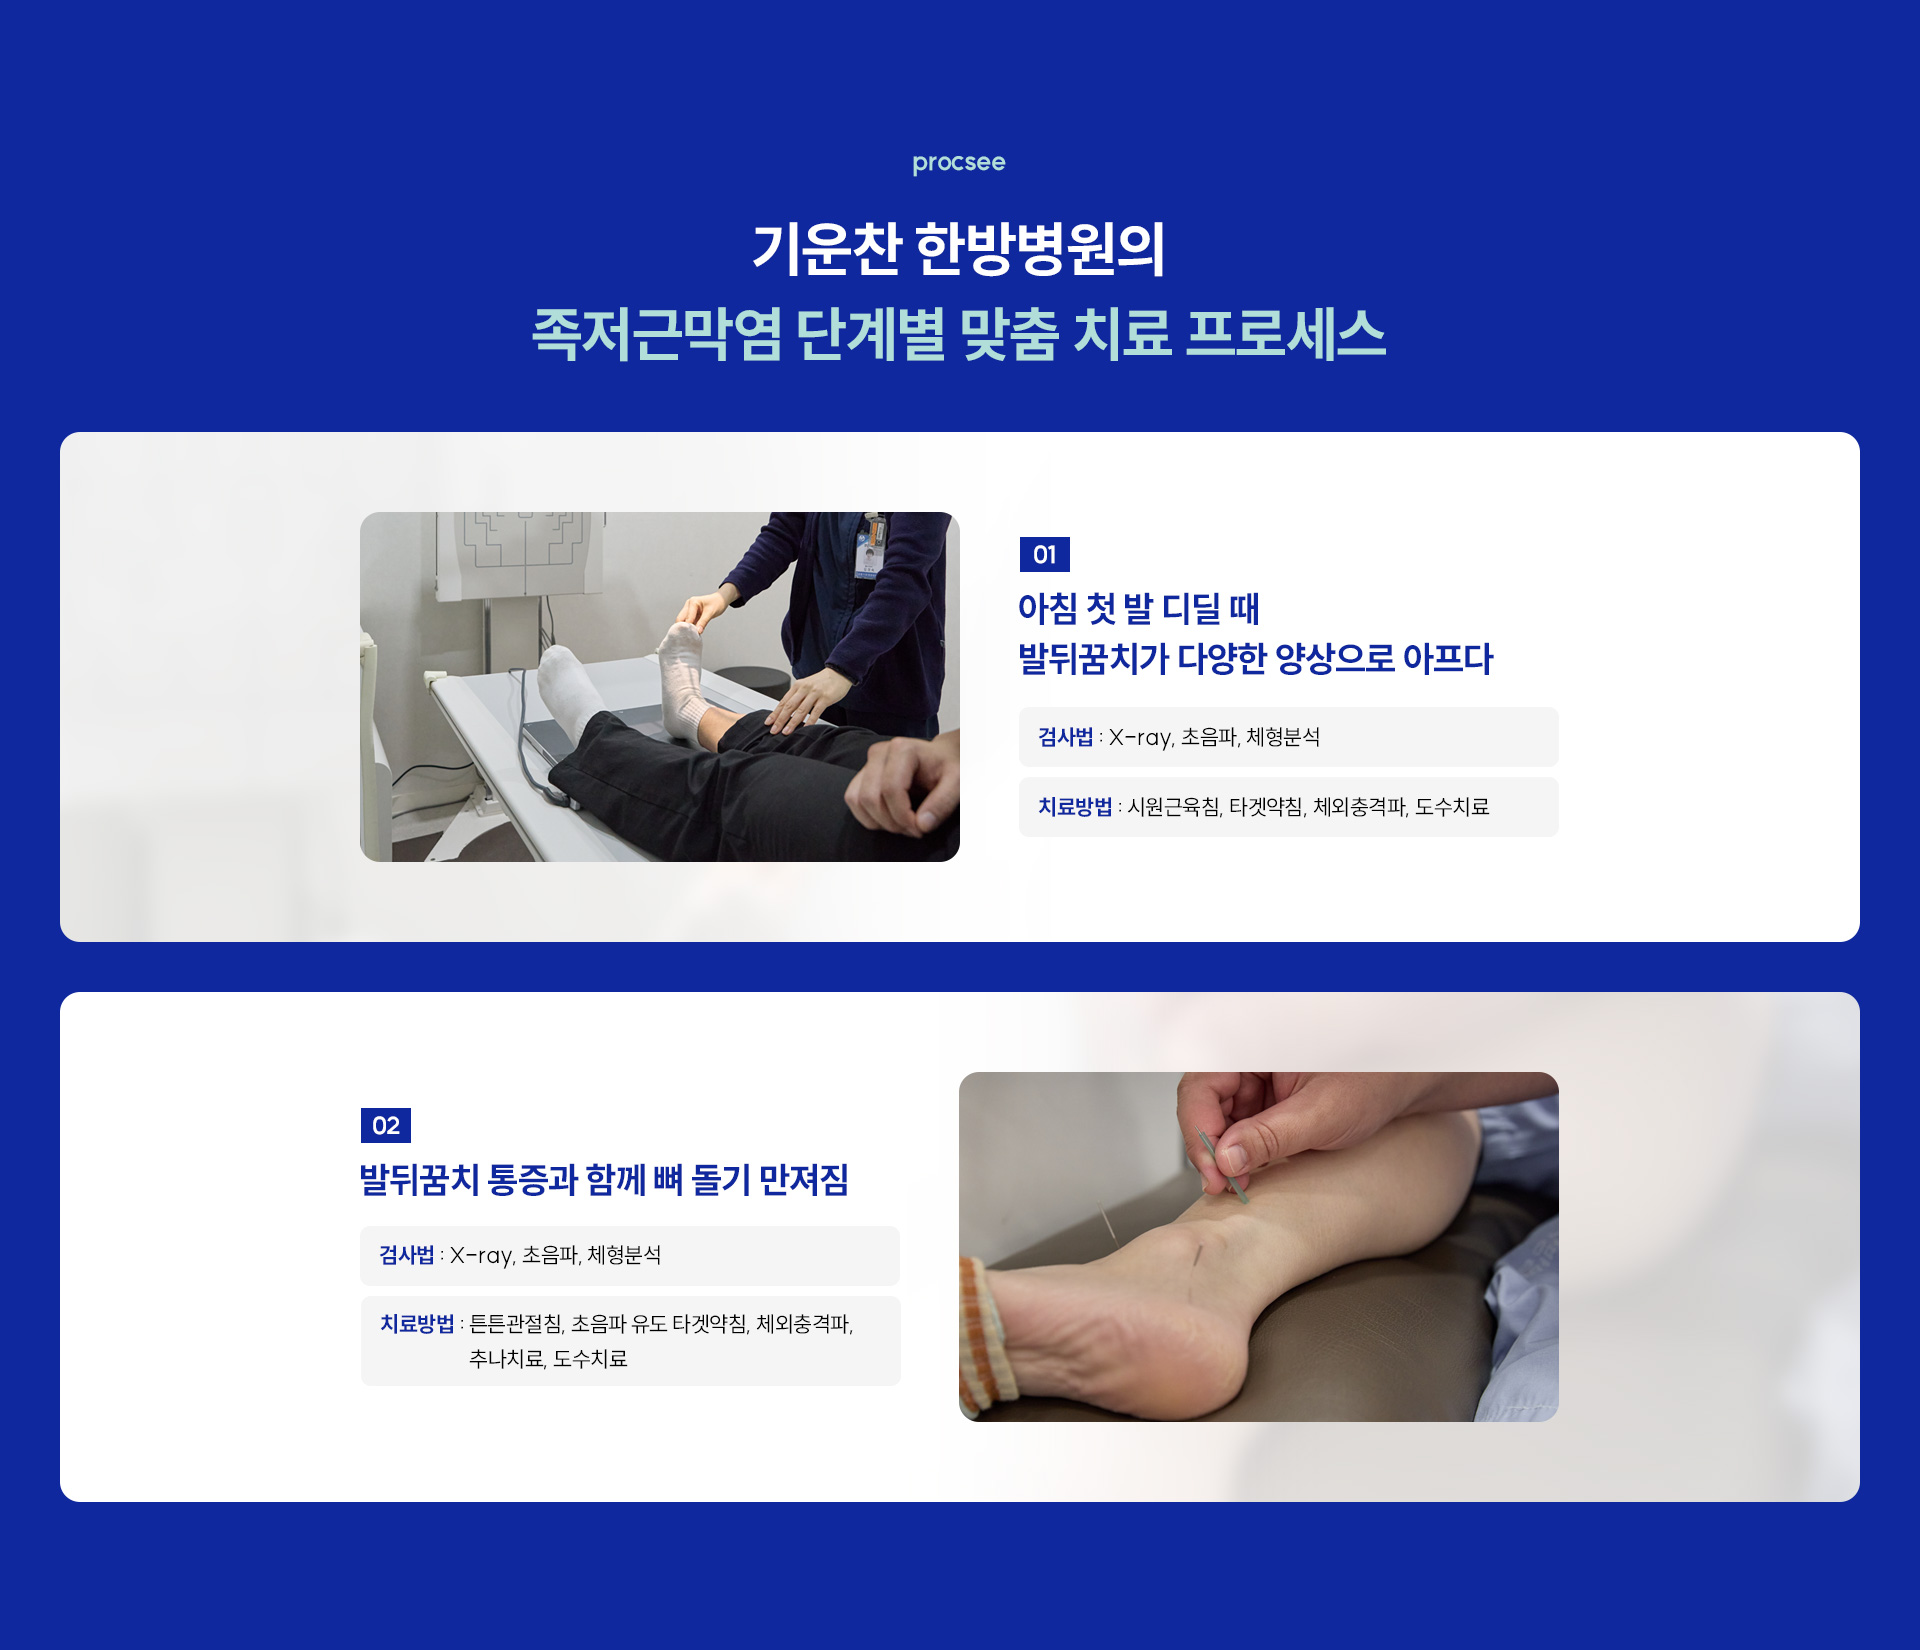

아침에 첫 발을 내디딜 때 발바닥에 찌릿한 통증이 느껴진다면, 족저근막염을 의심해볼 수 있습니다.

서 있거나 걸을 때 통증이 빠르게 심해지는 것도 특징 중 하나입니다.

이 질환은 치료를 미루면 쉽게 낫지 않고 만성 통증으로 이어질 수 있기 때문에, 초기 대응이 매우 중요합니다.

· 뒤꿈치 뼈 돌기(골극, Heel Spur)

: 족저근막에 염증이 오래 지속되면, 뒤꿈치 뼈에 돌기가 자라며 날카롭고 찌르는 듯한 만성 통증을 유발할 수 있습니다.

· 아킬레스건염

: 발뒤꿈치 주변 근육과 힘줄에 과도한 긴장이 반복되면, 염증으로 이어져 통증과 움직임의 불편함이 나타날 수 있습니다.